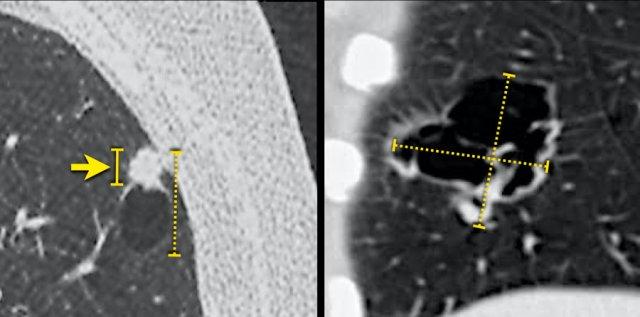

Các hình ảnh cho thấy một tổn thương tiền thân dạng nang nhỏ (hình bên trái) ban đầu được diễn giải là “hang thành mỏng, nhiều khả năng do nhiễm trùng”.

CT tiếp theo được thực hiện do ho 4 năm sau, cho thấy ung thư biểu mô tế bào vảy giai đoạn T4 (hình bên phải).

Bệnh nhân còn sống 2 năm sau phẫu thuật cắt bỏ và điều trị toàn thân.

Khả năng đánh giá quá mức gánh nặng khối u do tính cả thành phần khoang khí dạng nang vào kích thước tổn thương tổng thể, khi đo theo phân loại TNM ấn bản thứ 8 (đường nét đứt). Đường liền nét (hình bên trái) có thể phản ánh chính xác hơn thành phần khối u xâm lấn và tiên lượng liên quan.

Mặc dù ung thư phổi dạng nang có hình thái học đặc trưng, việc phân giai đoạn vẫn được thực hiện theo phân loại TNM ‘tiêu chuẩn’ ấn bản thứ 8th, vốn phân tầng các nhóm bệnh nhân dựa trên tiên lượng của họ.

Tuy nhiên, việc đo các tổn thương nang phức tạp trên CT có thể dễ xảy ra sai số, và có thể đặt ra giả thuyết rằng kích thước tổn thương tổng thể (bao gồm cả thành phần nang đôi khi rất lớn) sẽ đánh giá quá mức gánh nặng khối u thực sự, do thành phần đặc xâm lấn mới là yếu tố có liên quan nhiều hơn đến tiên lượng.